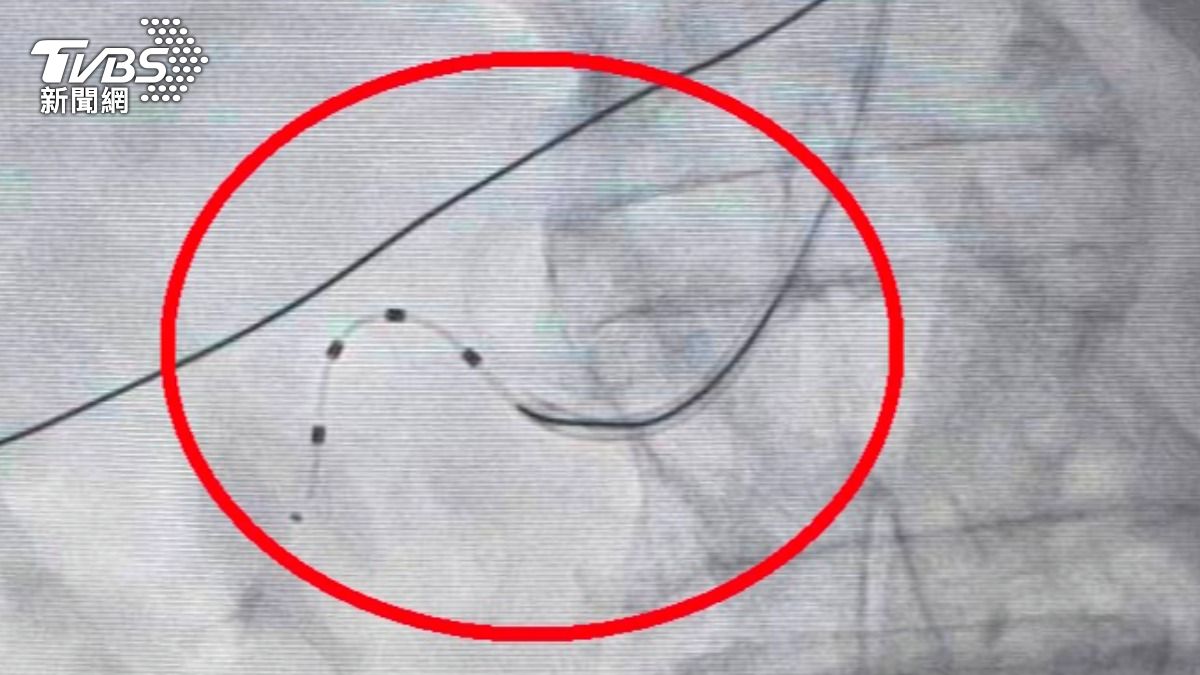

60歲的藝人何篤霖主持節目《命運好好玩》24年,今年卻被目擊到坐著輪椅下機,事後他也公開解釋,是當時膝蓋突然疼痛到無法走路,只好在機場內坐輪椅行動,目前已吃藥緩解。醫師提醒,雖然止痛藥能減輕關節疼痛,但最好還是就醫檢查,避免錯過黃金治療期。